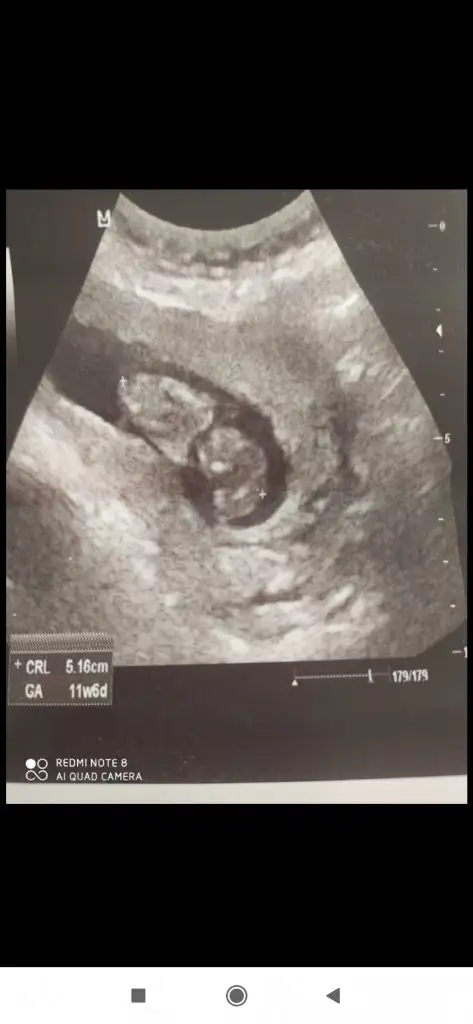

Kızlar bebek burda neye benziyor ikili tarama bu 😂

Screenshot_2020-10-09-19-44-08-603_com.kadinlarkulubu.kadinlarkulubu.webp